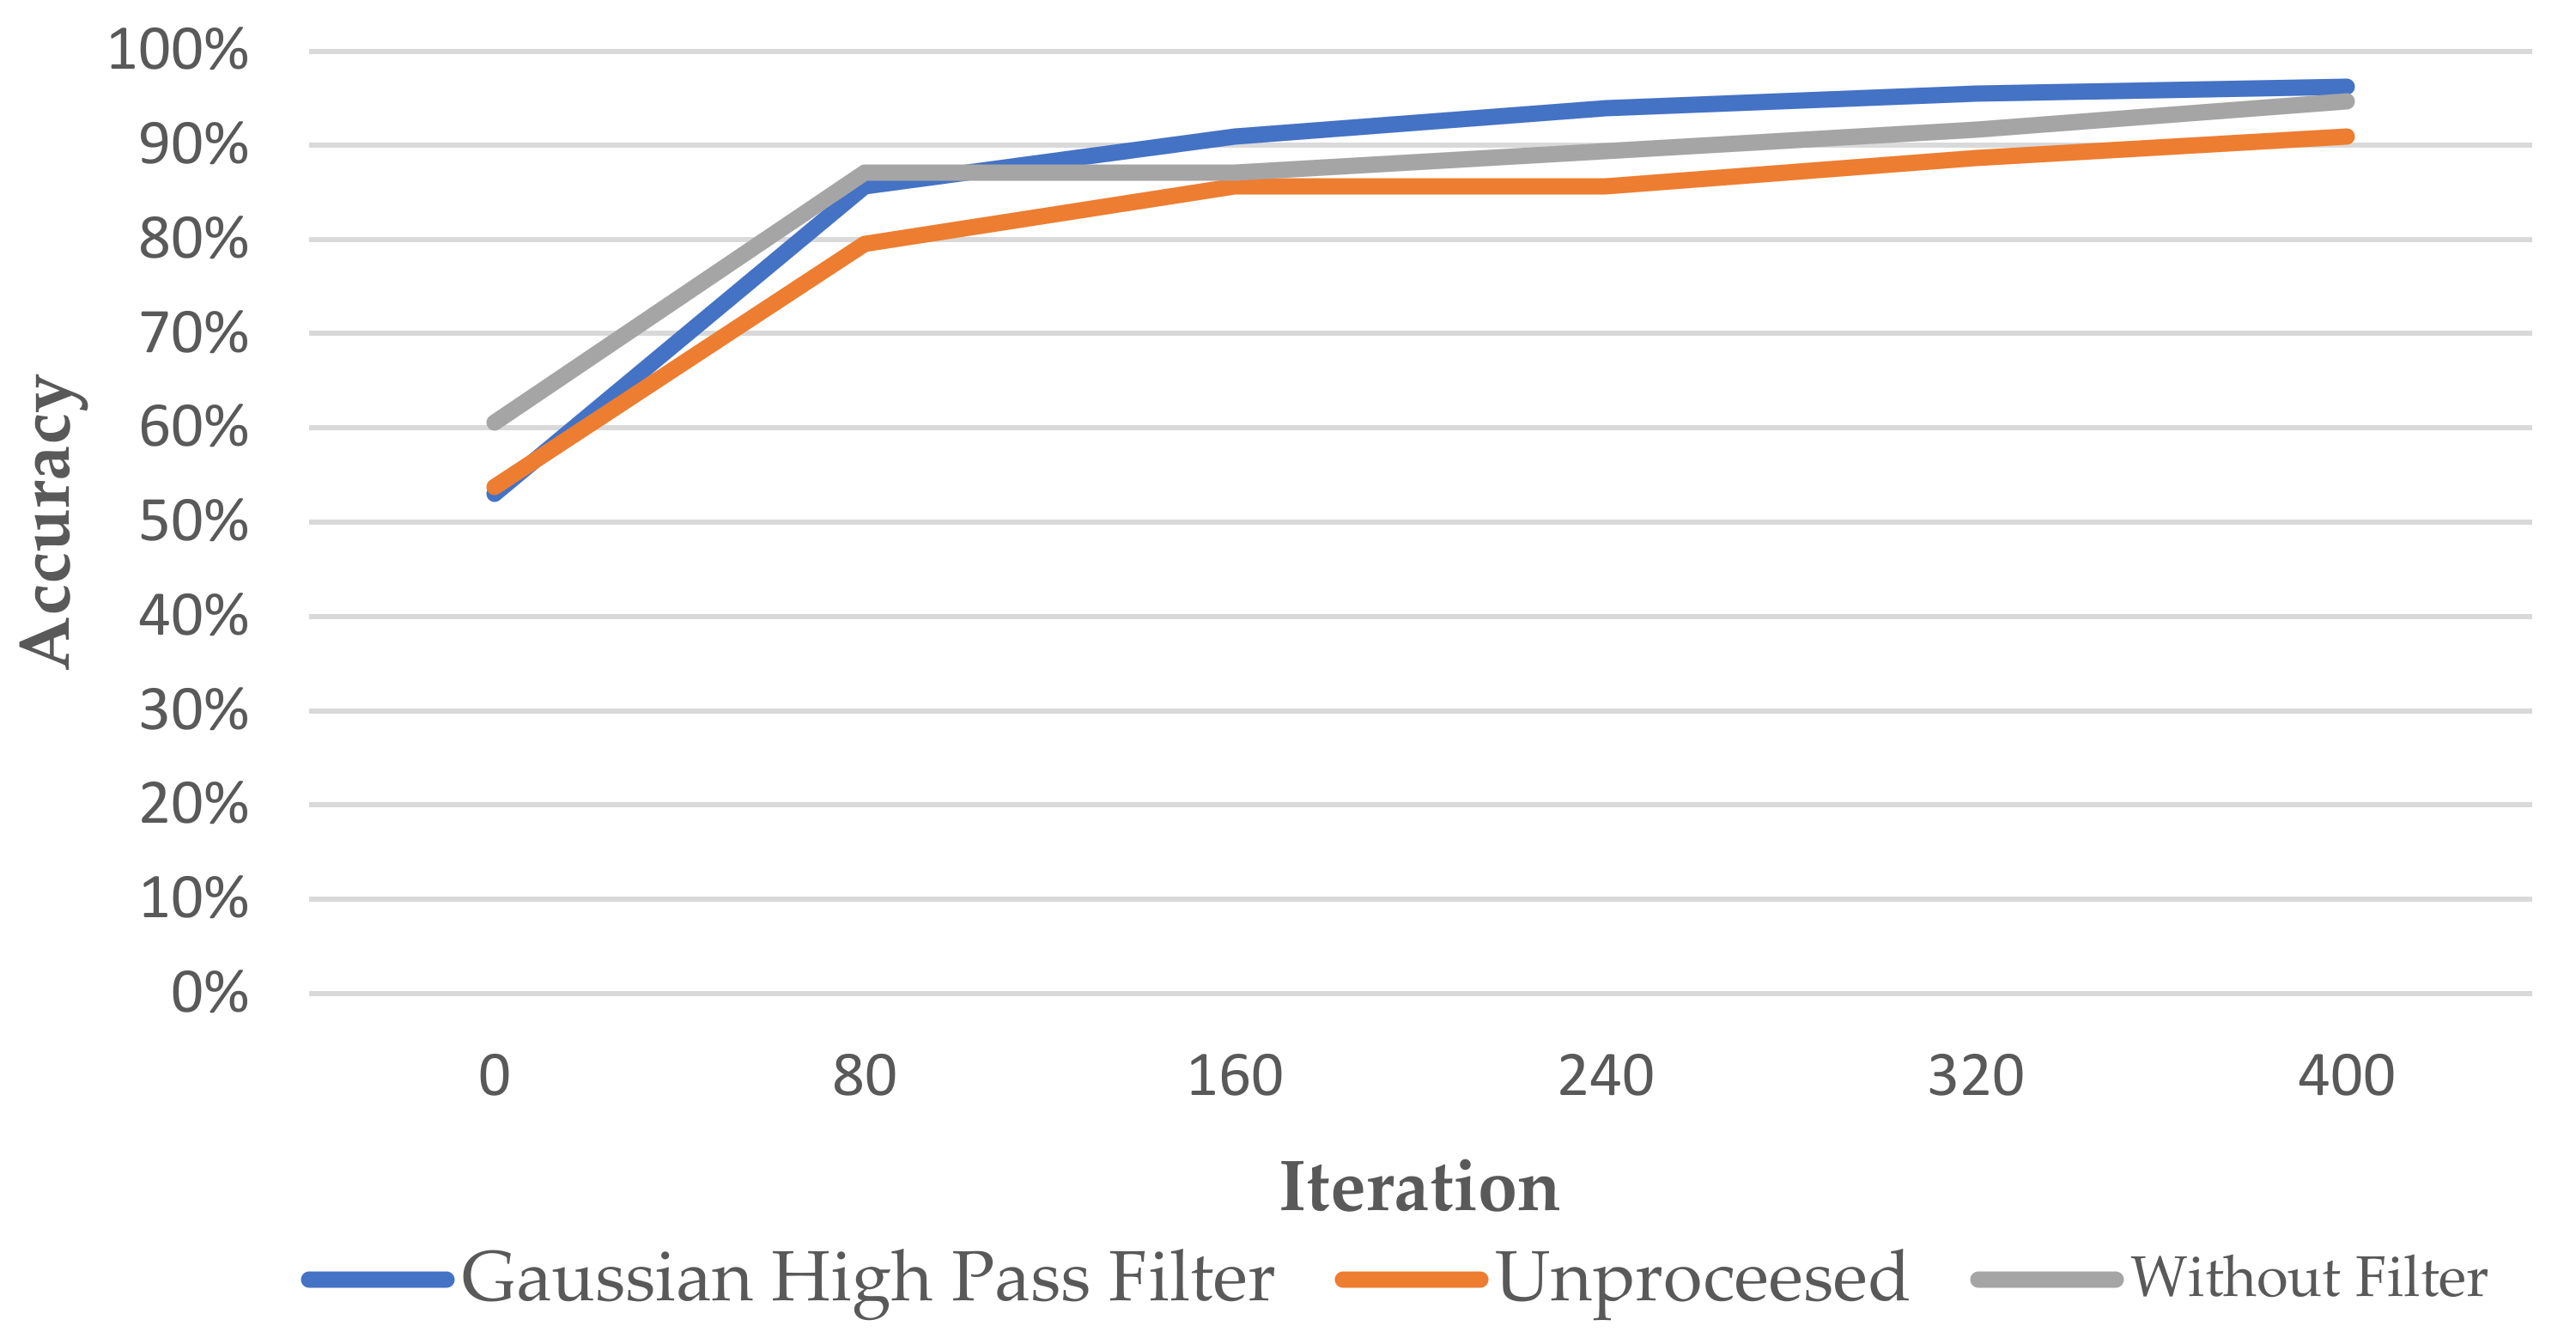

- This study proposes an advanced image enhancement technique for apical lesions. It adds raw grayscale images and Gaussian high-pass filtered images to highlight the possible lesion areas and changes the color of the possible lesion area to green. Experiments show that the accuracy of the model is improved by more than 10% which proves that the proposed method is intuitive and effective.

- The innovation of this work is to realize the classification of various diseases. It can simultaneously judge a variety of different types of dental diseases (such as apical lesions, fillings, etc.), and the obtained final accuracy of the model proposed in this paper is as high as 93%. AlexNet even improves the accuracy up to 96.21% which is 4% higher than the state-of-the-art in [23].

3. Results